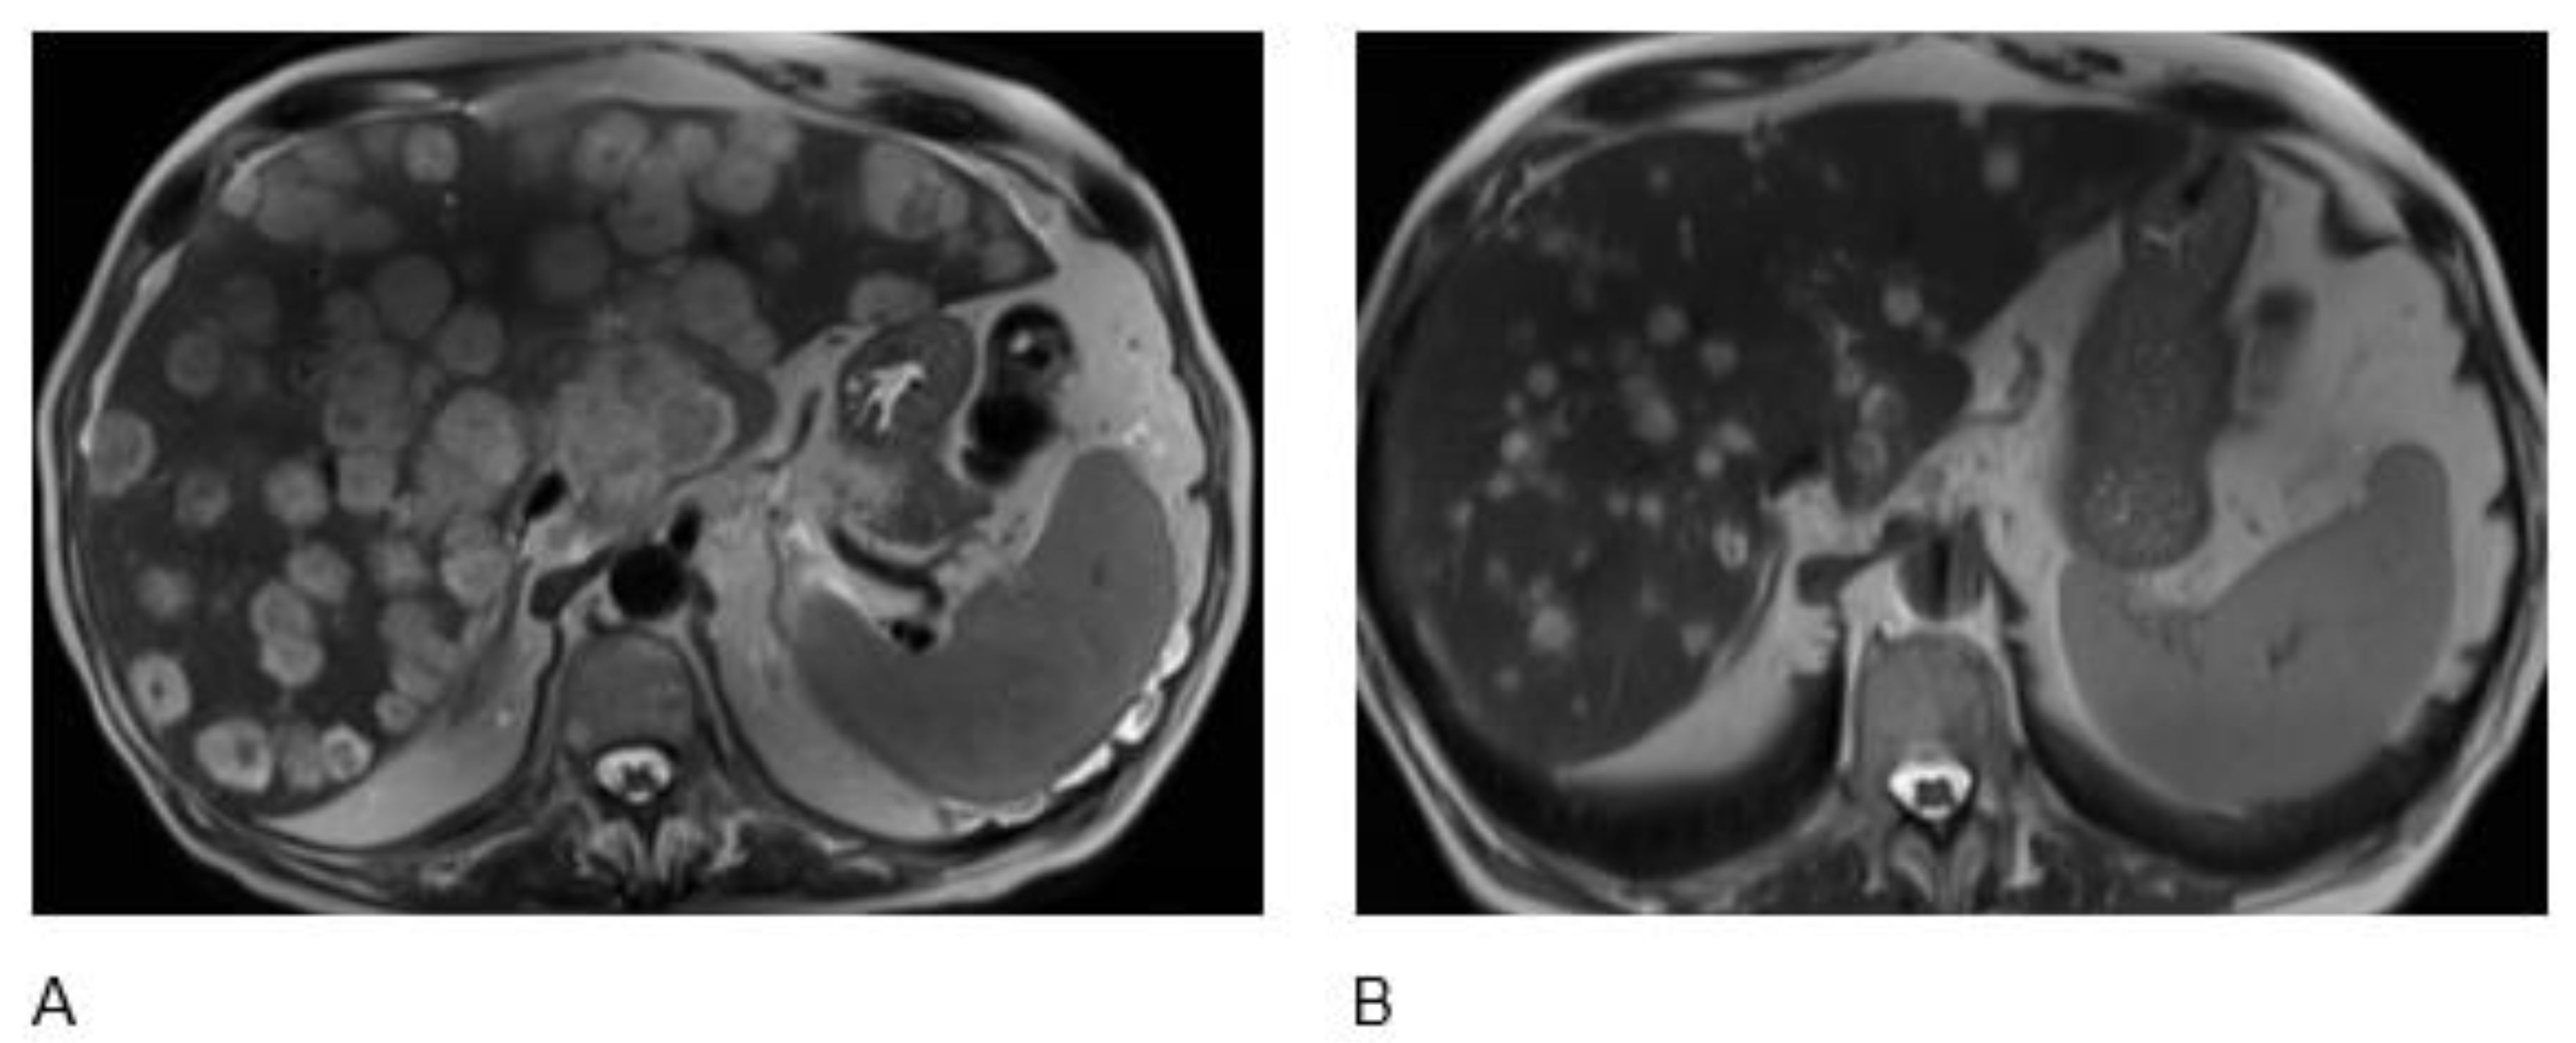

| Unknown Primary | EP Poorly differentiated neuroendocrine carcinoma (Small cell) | 77 | M | Carboplatin and Etoposide | Nivolumab 240 mg intravenous (i.v) every 2 weeks and Ipilimumab 1 mg/kg i.v. every 6 weeks for 4 cycles plus TQ-BSO (3 tablets 500 mg daily) | Nivolumab 240 mg i.v. every 2 weeks, plus BSO (TQ) tablets 1500 mg daily | Alive with PR and PFS of 24 mos |

| Gall Bladder | Poorly differentiated neuroendocrine carcinoma (Small cell) | 75 | M | Carboplatin and Etoposide | Nivolumab 3 mg/kg i.v and Ipilimumab 1 mg/kg i.v. every 3 weeks for 4 cycles plus TQ-BSO (3 tablets 500 mg daily) | Nivolumab 240 mg i.v. every 2 weeks, plus BSO (TQ) tablets 1500 mg daily | Alive with CR and PFS of 22 mos |